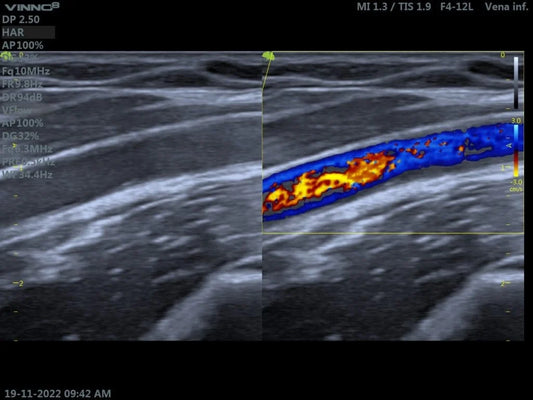

Ecografía Doppler en diagnóstico vascular: crit...

El desafío de la hemodinámica real: Más allá de la imagen en color En la práctica diaria de una unidad de diagnóstico vascular, nos enfrentamos a una realidad que los...